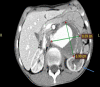

Thoracoabdominal aortic aneurysm (TAAA) is primarily a disorder of the elderly; the condition, however, is rare in children, for whom the misdiagnosis is not uncommon. It is one of the leading causes of death in the older age group worldwide, with a 4:1 male to female ratio. There are no real data about the incidence of aortic aneurysms in childhood. Although rare, an aortic aneurysm can be an important cause of mortality in children and adolescents. We present a case of an adolescent boy with a left coronary artery aneurysm, left axillary artery aneurysm, and TAAA type-IV caused by the metabolic disease homocysteinemia. He was referred to our facility when the complicated picture of the disease was discovered.